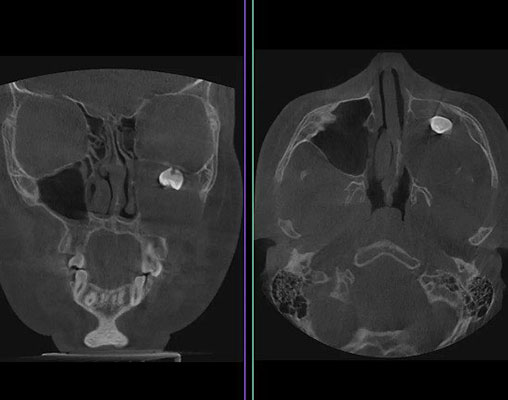

15-летний Артем поступил в Филатовскую детскую больницу с жалобами на асимметрию лица и заложенность левой полости носа. До этого в частной клинике пациенту сделали рентгенограмму и КТ, исследования показали, что в гайморовой пазухе находится полностью сформированный зуб. Врачи клиники предложили удалить зуб через нос и сделать коррекцию носовой перегородки, но мама мальчика решила обратиться за дополнительной консультацией в Филатовскую детскую больницу. В отделении оториноларингологии подростку была выполнена более углубленная компьютерная томография с большим количеством срезов, а также проведен консилиум с челюстно-лицевым хирургом. Врачей смутила клиническая картина заболевания, у них возникло подозрение, что дело в нарушении формирования зубной ткани.

«Нам необходимо было увидеть что происходит в гайморовой пазухе, поэтому мы выполнили мальчику операцию по Колдуэлу Люку, то есть, обеспечили доступ через верхнюю десну. Сделав разрез, мы обнаружили новообразование, внутри которого находился зуб, - рассказывает хирург-оториноларинголог Вугар Фазильевич Достиев, - позже по результатам исследования выяснилось, что это тератома.(тератома – это эмбринально-клеточная опухоль , внутри которой могут находиться элементы тканей, несвойственные этому участку тела – волосы, ногти, мышечные волокна, кости или зубы). Тератомы очень редко располагаются в зоне лица, чаще в крестцовой области. Ни КТ, ни рентген опухоль не показали, поскольку она занимала фактически всю левую полость носа. Наша осторожность полностью оправдалась, здесь было важно удалить новообразование единым комплексом.»